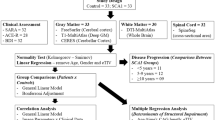

All statistical analyses, when not specified, were implemented on SPSS 13™ software statistical package (SPSS Inc., Chicago, USA; http://www.spss.com).

Groups comparisons

We used independent two tailed two samples t test (equal or not equal variance assumed on the basis of a Levene’s test) to compare means of demographic and neuropsychological scores of controls and SCA2. We also used an ANCOVA model with TIV, age and education as covariate and genotypes as factor to compare the Tower of London scores.

An ANCOVA model with age, sex, education, TIV as covariates and genotypes as two factor levels (SCA2, controls) was estimated with SPM8 for GM atrophy (no global normalisation and no grand mean scaling). We used an identical model to test WM atrophy. We tested two contrasts: controls > SCA2 and SCA2 > controls. We used these models on DARTEL (43 GM + 43 WM whole brain 8 mm smoothed modulated normalised images), SUIT (43 GM + 43 WM Cerebellum and Brainstem 4 mm smoothed modulated normalised images) and ROIs data (25 GM ROIs + 22 WM ROIs).

All the contrasts SPM maps were thresholded at an uncorrect p < 0.001. We make an additional request, to minimise false positives, to consider a voxel significant it should also belong to a cluster with a corrected cluster-level p corr ≤ 0.05, FWE corrected, by applying the Random Field Theory (Kiebel et al. 1999), for infratentorial clusters or FDR corrected (Benjamini et al. 2001) for supratentorial clusters. We used a more permissive cluster-level threshold only for extra-cerebellar voxels (as in Brenneis et al. 2003).

In the ROIs analysis we used the step-down Finner formula (FWE correction) to choice the significant group comparisons at ROIs level \( p_{\text{corr}} < 0.05:p_{\text{corr}} = 1 - (1 - p_{i} )^{{\frac{n}{i}}} \), where i is the ith smallest p value in the list and n are the number of considered comparisons (Finner 1990, 1993).

Correlations

Multiple regression models with age, sex, TIV and one variable of interest were estimated with SPM8 (no global normalisation and no grand mean scaling) for GM atrophy correlations with clinical, demographic, genetic and neuropsychological parameters. The considered variables of interest were: disease duration, ICARS total score, CAG repeats, ToL PEG and ToL CPU, we tested all these one by one on DARTEL (43 GM + 43 WM whole brain 8 mm smoothed modulated normalised images) and SUIT (43 GM + 43 WM Cerebellum and Brainstem 4 mm smoothed modulated normalised images) data. We considered as significant voxels with an uncorrected p < 0.001 belonging to a cluster p corr ≤ 0.05 cluster-level corrected (FWE corrected for infratentorial voxels and FDR corrected for supratentorial voxels).

We calculated with the Pearson’s coefficient r the table of correlations between ROIs volumes (TIV normalised), ToL PEG, ToL CPU, demographics, CAG repeats and clinical parameters (means and SDs reported in Table 1). We used the step-down Finner formula (FWE correction) (Finner 1990, 1993) to determinate the significant correlations. To confirm our data we also tested some correlation that was already consistently reported in literature.